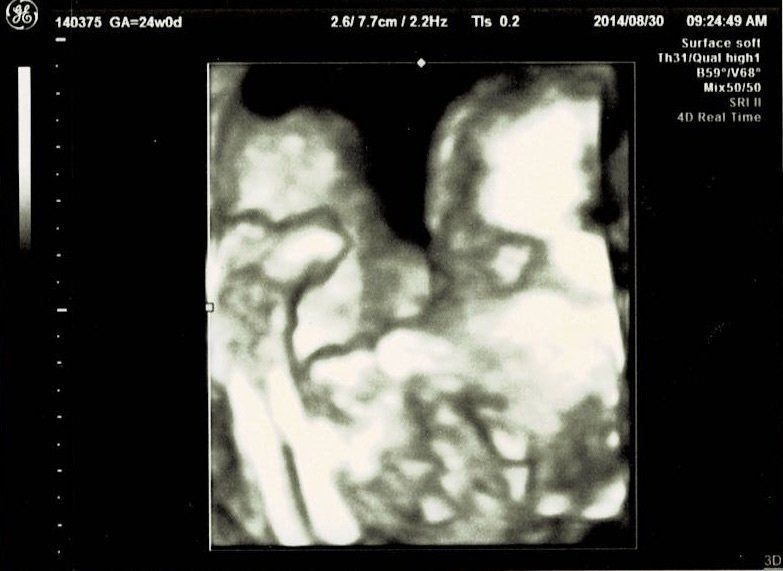

妊娠24週目エコー写真 お顔がなかなか見られない 夏の妊娠はとにかく暑い

夏真っ盛り。妊娠前の半袖ワンピースでどうにか乗り切っていましたが、腹帯なんて暑いものは耐えられず取ってしまいました。妊娠16周目と同じく、BPD、AC、FLを測ってもらいました。赤ちゃんのおおよその体重は606g。3Dエコーでお顔をきちんと見てみようとしますが、やはり手で隠してしまうため、なかなか見られませんでした。これでも顔が写っている一番いい3Dエコー写真です。